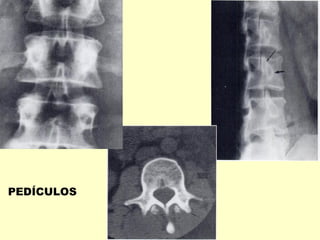

Os pedículos

vertebrais são sede

preferenciais de

implantes metastáticos

METÁSTASE ÓSSEA

PEDÍCULOS

PEDÍCULOS LOCAL COMUM DE METÁSTASES ÓSSEAS

METÁSTASES OSTEOESCLERÓTICAS/NEO PRÓSTATA